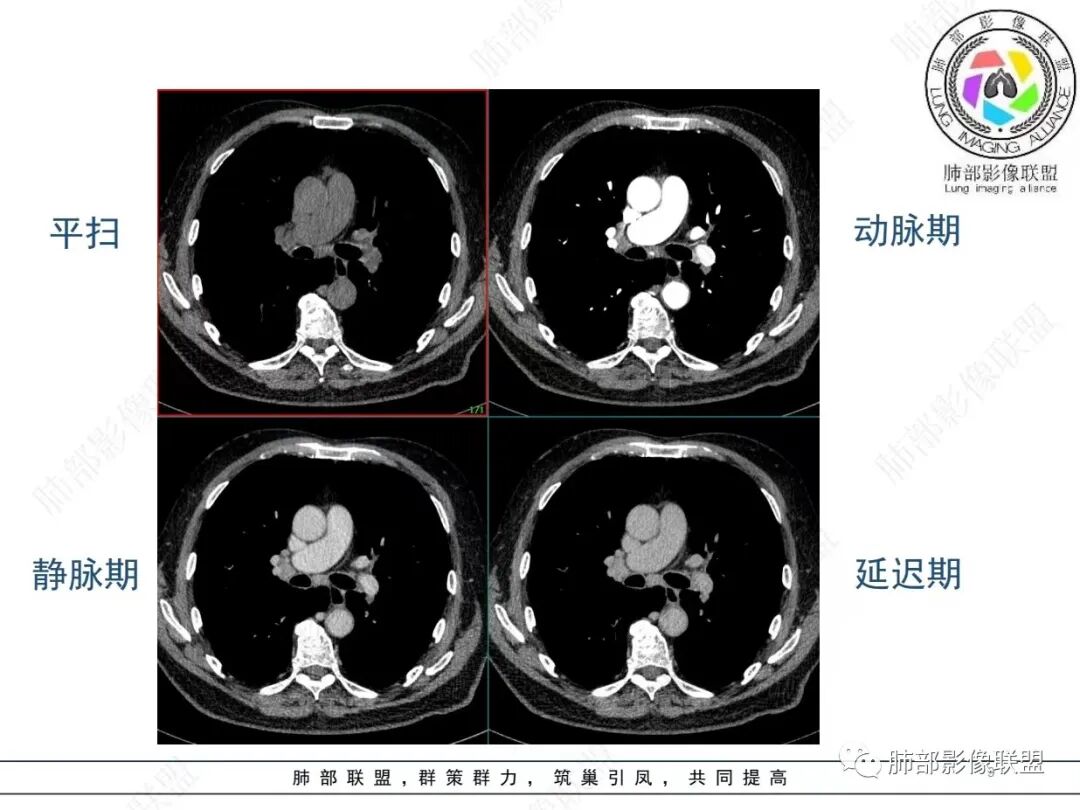

老年男性,发作性气喘,实验室检查白细胞增高。肺部影像表现:右肺胸膜下占位性病变,肺气肿背景,内部可见空腔/空泡影,周围可见小结节,增强动脉期明显强化,静脉期及延迟期强化减低,右侧肺门可见肿大淋巴结,有吸烟史,近年减少,首先考虑恶性肿瘤,肺小细胞癌/鳞癌,隐球菌作为鉴别诊断,病例穿刺活检。

老年男性,气短,胸痛半年,考虑慢性病史,无发热,常见的肺部感染可以排除,右肺下叶基地段靠近胸膜实变影,边缘清楚,不均匀强化,可见空泡征,点状血管影,周围小叶中央型结节,有网格影,支气管扩张,磨玻璃影,肺间质改变,右侧肺门淋巴结肿大,综合考虑恶性肿瘤并肺内转移

老年男性,胸疼入院,影像表现,右肺下叶胸膜下结节,边界清晰,与支气管关系不密切,病灶内见空洞?增强病灶均匀强化,右肺门可见增大淋巴结,考虑恶性病变,小细胞癌,其次鳞癌

老年男性,肺气肿背景,右肺下叶,右肺下叶胸膜处实性结节,形似山丘,有分叶,病灶内可见扩张细支气管/空泡,边缘可见弯曲血管,增强后不均匀强化,可见血管影,病灶胸膜侧呈小波浪??状,局部突入胸膜面,右肺门肿大淋巴结。考虑恶性结节,小细胞肺癌,腺癌,鉴别炎性肉芽肿。建议ct下穿刺活检。

老年男性,肺气肿病史,支气管束增粗,管壁增厚,右肺下叶后基底段胸膜下肿块,土豆征,边界清,有膨隆,小支气管边缘阻断,见集血管束征,肿块强化明显(快进快出特点),并偏心空洞,胸膜下栽赃,周围肺结构破坏(蜂窝状影表现),右肺门淋巴结转移肿大,血管内皮生长因子偏高,肿块与小支气管,血管束关系密切,强化特点,定恶性肺肿瘤,小细胞Ca。

老年男性,肺气肿,右肺下叶胸膜下结节,边缘毛躁,周围多发间质增厚,临近胸膜下脂肪间隙模糊,增强后动脉期不均匀强化,延迟期强化较低,右肺门肿大淋巴结,考虑恶性,鳞癌,小细胞肺癌,鉴别炎性肉芽肿性结节

右肺下叶胸膜下结节,边界清,边缘平直膨隆,血管集束,其内空洞,明显不均匀强化,考虑腺癌?小细胞癌?鉴别隐球菌

肺气肿,胸膜下结节,边界清晰,边缘毛糙,病灶内见空洞,增强病灶均匀强化,右肺门可见增大淋巴结,考虑恶性病变,小细胞癌,其次鳞癌,鉴别隐球

老年男性,肺气肿背景,右肺下叶胸膜下团块影,明显强化,其内空泡征,周边血管聚集,右肺门淋巴结增大,考虑腺癌?

右下叶胸膜下结节,宽基底与胸膜相连,结节与胸膜相交呈钝角〈山丘征〉,内可见充气扩张的支气管,中度强化,结节边缘无毛刺,内见走行自然的血管影,提示破坏力及收缩力差,右肺门可见肿大淋巴结,老年烟民,考虑恶性占位,支持小细胞癌

右肺下叶胸膜下结节,呈山丘状,生长在慢支肺气肿间质纤维化的基础上,边缘相对光滑清晰,右肺门淋巴结肿大,强化呈速升速降,老年男性,吸烟史,考虑小细胞肺癌,鉴别隐球

老年男性,吸烟史40年,肺气肿背景,胸膜下结节,边缘膨隆,增强后结节内有片状坏死区,右肺门及纵隔肿大淋巴结,考虑恶性,鳞癌?小细胞代排

老年患者,右下肺胸膜下结节,有血管聚集、空泡征,强化明显,右肺门见肿大淋巴结。考虑腺癌,鉴别肉芽肿性病变

老年男性,长期抽烟病史,右下肺胸膜下结节,有分叶,胸膜下栽桩,肿块增强可见明显不均匀强化,考虑恶性,鳞癌可能性大,鉴别小细胞肺癌。

恶性明确(右肺门淋巴结明显肿大,中心坏死,坏死边界不清楚,胸膜下馒头样肿块,血管集束,支气管阻塞,动脉期明显强化,内部明确的供血血管提示肿瘤细胞密集,局部坏死边界不清,强化快进快出,邻近胸膜强化呈胸膜尾征,提示胸膜受侵),病理符合周围性低分化鳞癌(老年男性,长期吸烟史,肿块强化明显,快进快出,坏死边界不清楚,阻塞性炎症及阻塞性肺气肿,肺门淋巴结肿大,坏死,邻近支气管壁增厚支持粘膜下侵润生长),白细胞总数高,动脉期强化那么明显,腺癌合并感染倒是要高度警惕。

老年男性,吸烟史+肺气肿背景,右下肺胸膜下肿块(坏死+内部血管影+快进快出),右侧肺门淋巴结肿大,考虑:恶性、鳞?高级别腺待排(总体感觉偏软)。

男,80,发作性气喘半年,加重1天。长年大量吸烟史。肺部CT:肺气肿背景,右肺胸膜下实性占位,处于外周大疱带与气肿带交界,山丘征,边缘膨隆,边界较清,血管集束,周围可见小结节。增强不均匀强化,内可见迂曲模糊血管影,右肺门、隆突下可见肿大淋巴结。首先考虑恶性肿瘤,小?鳞?鉴别PC、TB等。